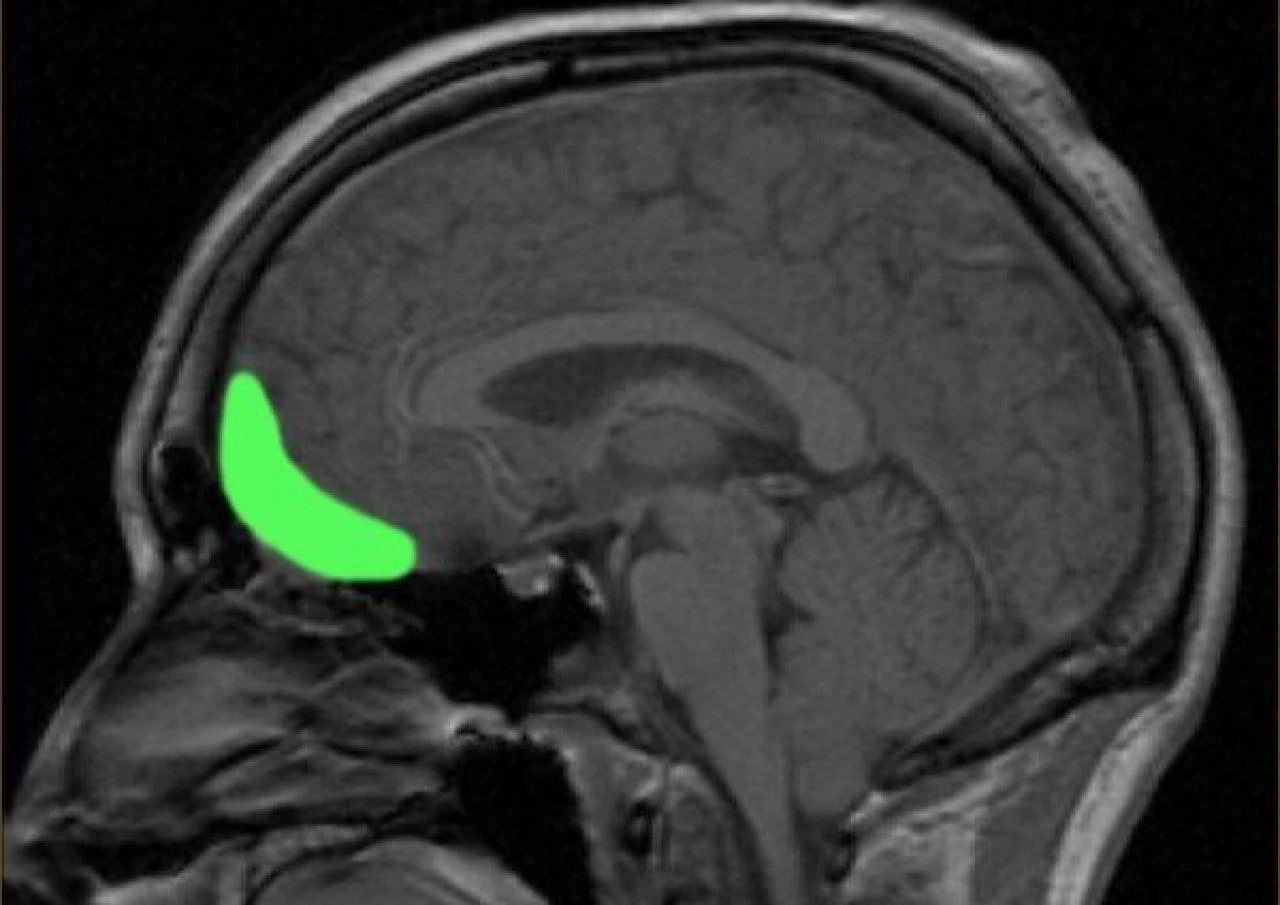

Almanca'da 'şaka' ve 'bağımlılık' kelimelerinin birleşimi olan Witzelsucht terimi ilk kez 1890 yılında, Hermann Oppenheim adlı bir Alman nörolog tarafından ortaya atıldı . Oppenheim, sağ frontal lobda oluşan hasarın, yaralanma ya da hastalık nedeniyle, hastalarında bazen aşırı komik davranışlara yol açtığını fark etti.

1929 yılında Alman beyin cerrahı Otfrid Foerster uyanık bir hastaya beyin ameliyatı yaparken , beynin belirli bir noktasına yaptığı müdahale sonucunda hasta aniden Latince, Yunanca, İbranice ve Almanca kelime oyunları yapmaya başladı.